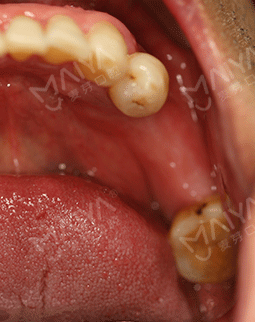

现在牙齿好了,吃东西特别香,气色好了很多,人也帅气不少,连整个人都精神百倍。与朋友相聚、出差摄影旅游啥的完全不担心这个吃不了,那个不能啃,现在啃排骨、吃螃蟹完全不是事。

这周约好了去医院复诊,虽然要去医院进行长期的牙齿维护,但是为了牙齿的健康,还是得坚持,毕竟牙齿陪伴一生,没有了它吃什么都没味道。真的非常感谢麦芽给了我再尝美味的机会。